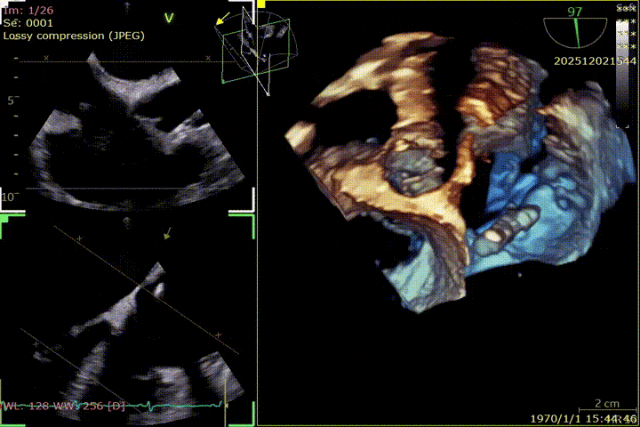

During the procedure, close collaboration was maintained with Dr. Yang Yan (anesthesiologist, Department of Anesthesiology) and Dr. Niu Ming (echocardiography specialist, team of Director Zhai Hong, Department of Cardiac Ultrasound). Guided by transesophageal echocardiography and assisted by DSA imaging, the tricuspid annular structure and regurgitation jet direction were precisely assessed. Ultimately, two 12T K-Clip® devices were successfully implanted. Immediate postoperative echocardiographic evaluation showed a significant reduction in tricuspid regurgitation from 4+ preoperatively to 1+, with a marked decrease in annular area. The surgical outcome was satisfactory.

The same procedure was performed for the second clip:

Anchor screw of the second clip advanced into the annulus.

Coronary angiography after the deployment of the second clip.

Surgical Outcome

Preoperative Regurgitation: 4+

Annulus Area: 11.3 cm²

Postoperative Regurgitation: 1+

Annulus Area: 4.9 cm²